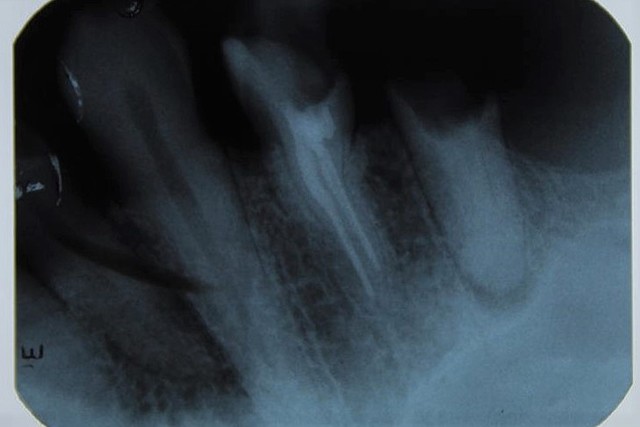

• Serie radiográfica

Serie radiográfica

En esta cita se tomaron 14 radiografías periapicales, que servirán de apoyo para un diagnóstico adecuado periapical de los órganos dentarios. En el órgano dentario 1.4 se encontró una endodóncia previa sin obturación y en la pieza 1.5 se encuentra sin corona dentaria, con ensanchamiento periodontal y una lesión apical.